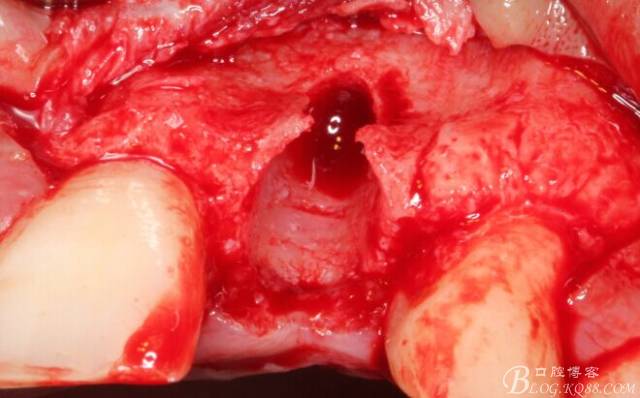

于是我果斷告知患者,手術(shù)失敗了,不能拖延,如不及時(shí)處理,炎癥繼續(xù)發(fā)展會(huì)很快波及鄰牙牙槽骨?;颊呓邮芪业慕ㄗh。切開(kāi)翻瓣,骨粉及生物膜消失了,骨吸收嚴(yán)重,幸運(yùn)的是,因?yàn)樘幚砑皶r(shí),鄰牙骨支持依然存在。

徹底掻刮。